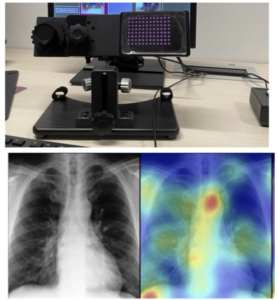

GazeGNN: A Gaze-Guided Graph Neural Network for Chest X-Ray Classification.

Authors: Wang, Bin, et al.

WACV 2024

Publication Year: 2024

EyeSee: Integrating Deep Learning for ImageAnalysis

Authors: Bin Wang and Ulas Bagci

Medical Image Perception Society (MIPS) XX 2024.